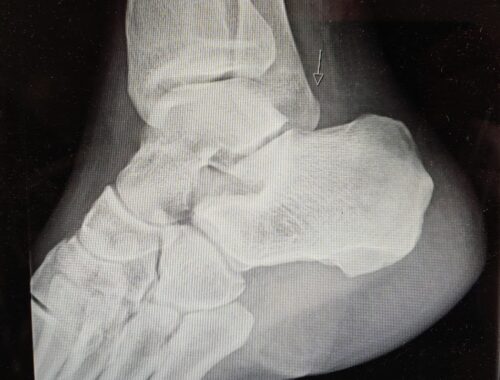

• Statusuppdatering om min ankel/fot

Idag har jag träffat sjukgymnasten Calle, så jag tänkte uppdatera er om min status med min ankel/fot. Som ni kanske kommer ihåg så ramlade jag i augusti då vi var på MTB semester i Funäsdalen. Slog mig rätt illa och…